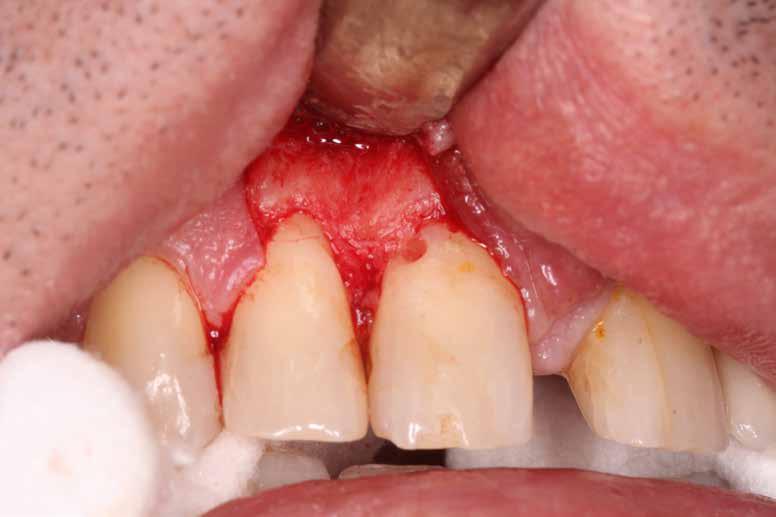

Ötvenes éveiben járó hölgyet fogorvosa irányította hozzánk a bal alsó 4-es fogának nagy méretű reszorpciójával [9. kép]. A hölgy ragaszkodott foga megmentéséhez, így a kezelés megtervezéséhez CBCT felvételt készítettünk a fogról [10. kép]. A felvételen a Patel-féle klasszifikáció szerinti Patel 3Ap reszorpciós elváltozás látható. A szájüregi vizsgálat során a fog bukkális felszínén gyulladt ínyt, mély parodontális tasakot és a fog nyaki részén, a foganyagon átsejlő reszorpciós lacunát találtunk [11. kép]. A fog szenzibilitás vizsgálat során nem reagált hideg ingerlésre. A pulpális érintettség miatt elvégeztük a fog trepanálását, majd lebenyt alakítottunk a kavitás láthatóvá tételéhez [12. kép]

Az üregben nagy mennyiségű gyulladásos szövetet találtunk, mely eltávolítása után láthatóvá vált a kavitás kiterjedése [13. kép]. A kisőrlő fogakra jellemző tengelyirányú, valamint oldalirányú terhelés kombinációja, valamint a jelentős foganyagveszteség miatt szerettük volna a lehető legjobban megerősíteni a fogat. A terület kofferdám gumilepedővel történő abszolút izolálása után a gyö-

kércsatornát egy guttapercha segítségével kiblokkoltuk, ezzel megelőzve a csatorna obliterálódását [14. kép]. Ezután megfelelő adhezív előkezelést követően kompozit tömőanyaggal restauráltuk az elváltozást (Essentia Universal, GC Europe) [15. kép]. Finírozást és alapos polírozást követően zártuk lebenyünket, majd újabb kofferdám izolálásban elvégeztük a fog gyökérkezelését [16. és 17. kép]. A kezelést követően páciensünk teljesen panaszmentes

volt. Két hónapos kontrollon a fog teljesen ép, az íny tökéletes kitapadását tapasztaltuk [18. és 19. kép]. Szondázási mélység a bukkális oldalon mindenhol 2 mm alatt volt.